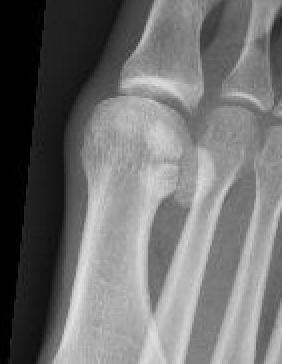

Imaging

Bilateral standing xray can help

Unclear if bipartite or stress fracture

Irregular borders suggest fracture rather than bipartite

CT demonstrates irregular borders consistent with fracture of tibial sesamoid